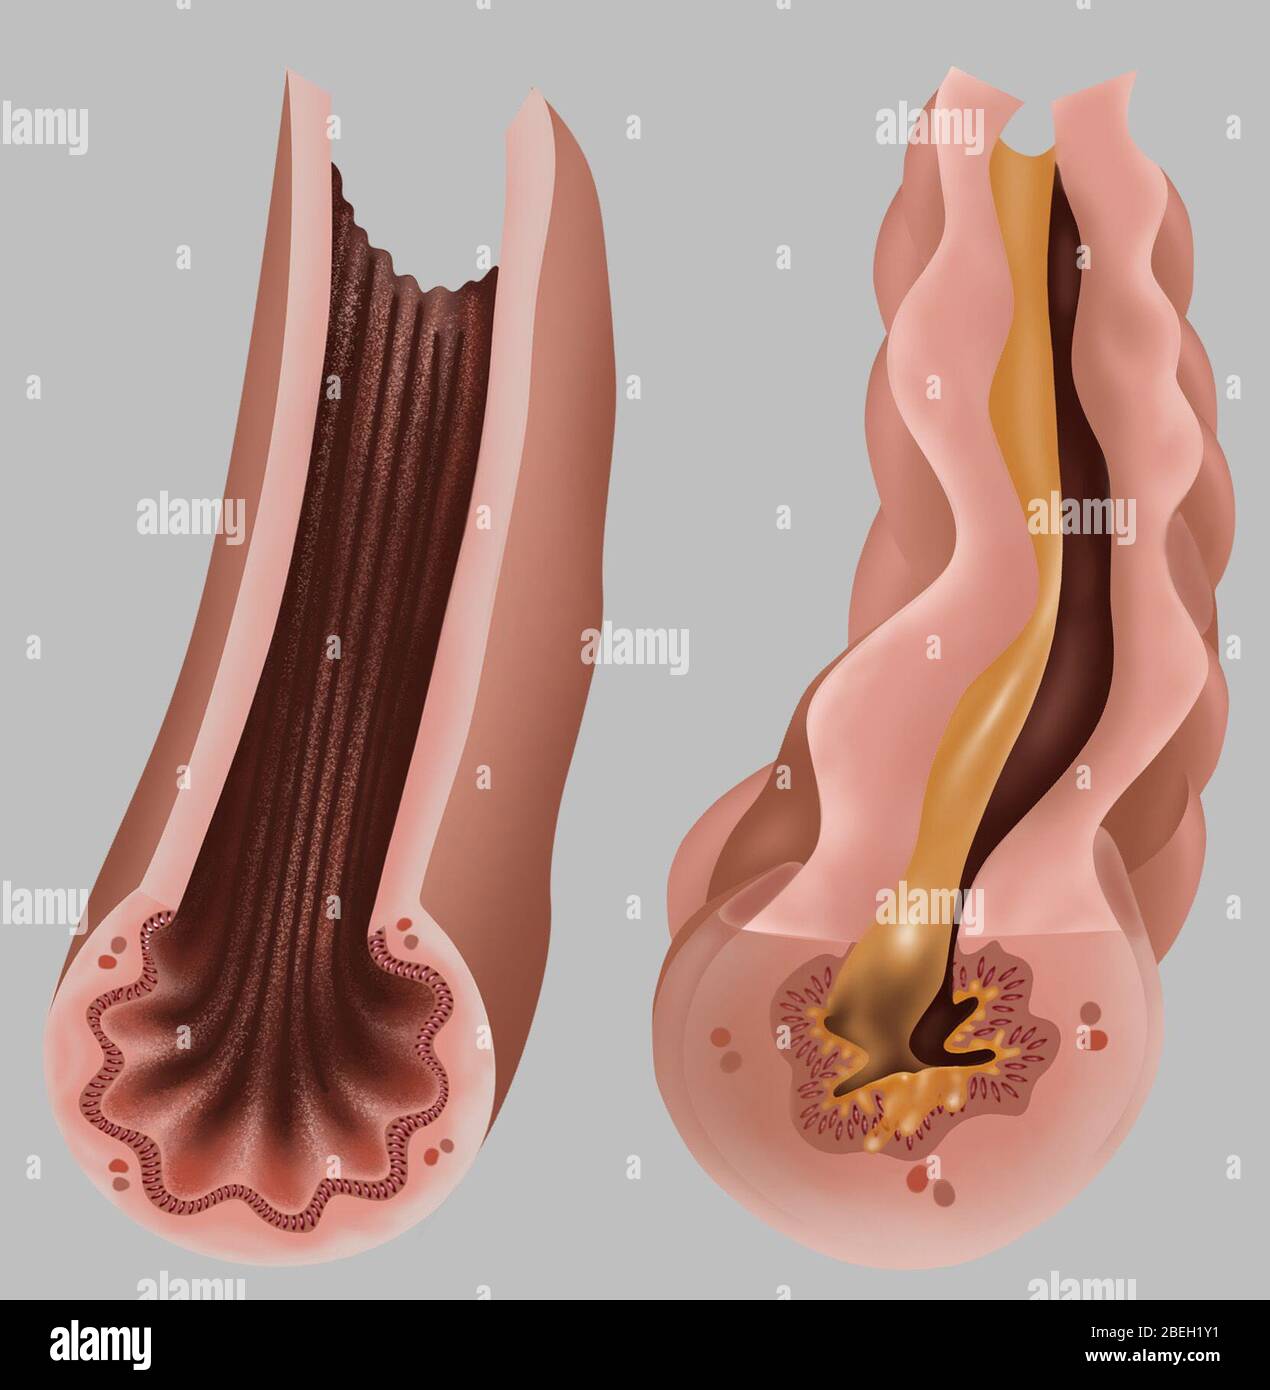

Asthma Pathology Stock Photohttps://www.alamy.com/image-license-details/?v=1https://www.alamy.com/asthma-pathology-image353187269.html

Asthma Pathology Stock Photohttps://www.alamy.com/image-license-details/?v=1https://www.alamy.com/asthma-pathology-image353187269.htmlRF2BEH1Y1–Asthma Pathology